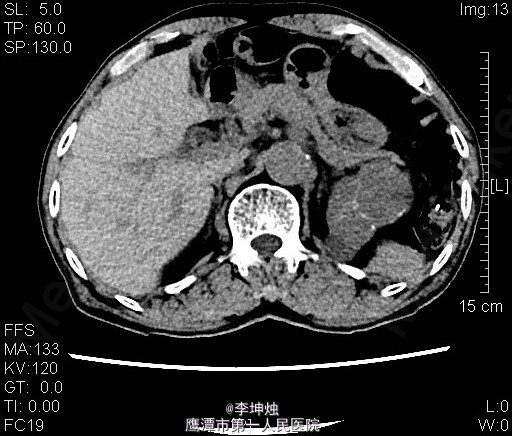

3、查体:增加腹压或站立位时右侧腹股沟隆起,可触及一大小约4*5cm肿物,可进入同侧阴囊,质软,边界清,无压痛,压迫肿物表面后嘱患者咳嗽,有冲击感,平卧或用手可将肿物回纳腹腔。直肠指检:肛门括约肌稍松弛,前列腺明显增大,大小约:3×4cm,表面光滑,质韧,边缘清楚,中央沟变浅,未触及明显结节,指套未见染血。 4、辅助检查:当地人民医院,腹部CT提示考虑左肾Ca可能;慢性膀胱炎;右侧腹股沟区见肠管嵌如;前列腺增生。我院双肾CT平扫+增强:左肾上极肿块,考虑肾癌,侵犯左肾上部皮髓质及左肾上盏,可疑侵及胰尾部。

5、诊断:左肾占位,左肾ca? 6、处理:入院完善相关检查,核素肾动态显像:双肾灌注轻度降低、功能中度受损。双肾+肾上腺CT:左肾上极肿块,考虑肾癌,侵犯左肾上部皮髓质及左肾上盏,可疑侵及胰尾部。排除手术禁忌后,行“腹腔镜下左肾根治+肾门淋巴结清扫术”,术后予“头孢哌酮钠舒巴坦钠(舒普深)”抗感染、抑酸、营养补液等处理,术后恢复可。病理提示嗜酸性细胞瘤。